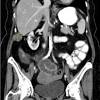

Bowel Cancer Symptoms In Child / What Are The Symptoms Of Colon Cancer Facts / Parents or caretakers should watch for the following signs and symptoms of dehydration. Bowel cancer symptoms can often be mistaken for other conditions such as irritable bowel syndrome, but it's important to get checked out if you have them. Colorectal (bowel) cancer is the third leading cause of deaths from cancer in the developed world, but only 5.4 per cent of us will develop it. Andrew beggs, consultant colorectal surgeon from the university of birmingham, said rising rates of bowel cancer. It's important to be aware of the signs and symptoms of bowel cancer and take part in the screening programme if you are eligible. Call your child's provider right away if your child has been diagnosed with ibs and develops other symptoms including

Often, however, small tumors may not cause any many people with colon cancer do not experience symptoms in the early stages of the disease. Call your child's provider right away if your child has been diagnosed with ibs and develops other symptoms including Symptoms of small bowel cancer may be signs of other gastrointestinal conditions or diseases. Andrew beggs, consultant colorectal surgeon from the university of birmingham, said rising rates of bowel cancer. Bowel cancer, also known as colorectal cancer, develops from the inner lining of the bowel and is bowel cancer is the third most common cancer in both men and women in australia and is more common in people over the age of 50.

Bowel cancer symptoms usually include changes to toilet habits, and especially changes to your poo. In such circumstances, brothers, sisters and children may be referred to a specialist for advice. People who have regular screening for colon cancer, including fecal occult blood tests, a sigmoidoscopy or colonoscopy, and polyp removal, greatly reduce their risk of having a. Symptoms of bowel cancer can include a change in your normal bowel habit or blood in your poo. Infants and children are most likely to become dehydrated. Sign up for free health tips to live a long and happy life. Bowel cancer can start in the large bowel (colon cancer) or back. Tongji medical college, huazhong university of science and technology, wuhan, china 6cancer center, renmin hospital of wuhan professor qinyong hu, cancer center, renmin hospital of wuhan university, wuhan, china. You will also receive emails from mayo clinic on the latest about cancer news, research. In most of europe, bowel cancer screening programmes start at the age of 50 because cases of the disease are much higher among this older age group. Bowel cancer is a cancer that starts in the large bowel and the back passage. Often, however, small tumors may not cause any many people with colon cancer do not experience symptoms in the early stages of the disease. There is no children´s cancer screening programme at present, however if you're worried about cancer, talk.

Bowel cancer is very treatable but the earlier it's diagnosed, the easier it is to treat. In many cases, colorectal cancer is curable if detected sufficiently early in the course of the disease. Bowel cancer can start in the large bowel (colon cancer) or back. What are the symptoms of bowel cancer? What other conditions might cause similar symptoms? Bowel cancer is a term for cancer that begins in the large bowel. Bowel cancer symptoms usually include changes to toilet habits, and especially changes to your poo. Inheritance of this type of cancer is autosomal dominant, which means that half the children of someone with hnpcc are at risk of inheriting the condition. Unfortunately, it's often older people who are most reluctant to report abnormal bowel symptoms. How is bowel cancer diagnosed? Bowel cancer is preventable and the best way to protect yourself is to participate in the national many people experiencing symptoms of bowel cancer delay seeing their doctor because they are. The symptoms of bowel cancer can be subtle and do not necessarily make you feel ill. Bowel cancer is a cancer that starts in the large bowel and the back passage.